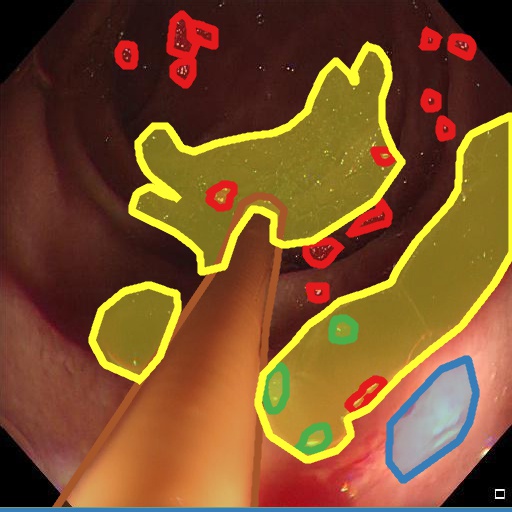

Examples for bounding box annotations for detection are shown in Fig. 2. It can be observed that while multiple boxes are annotated for several small specular areas; contrast, blur and instrument have relatively larger areas. Due to the overlap between two or more classes, the annotation by experts varied. This was minimized by following the detailed annotation protocol above. For semantic segmentation, a larger area mask was preferentially used to delineate locally very cluttered small specularity artifacts (see Fig. 3).